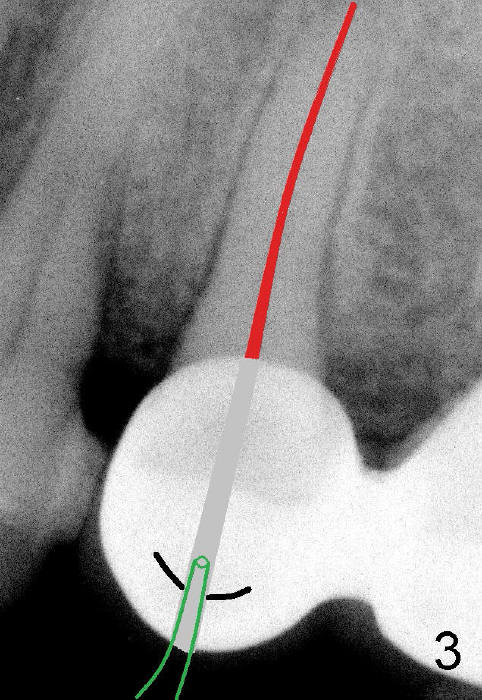

图二显示我们已经打开根管(灰色部分),黑线代表陶瓷牙金属部分,一旦水接触金属,Apex locator就不好用了。如果我们有一种方法使根管中水(图三红色)低于金属,Apex locator就能施展本领。我们在根管开口处插入外科吸管(图三绿色),水可以很快吸掉,水不再接触陶瓷冠金属。

在倪先生五号牙根管治疗中,我们使用外科吸管,Apex locator很容易使用,插入主牙胶尖(图五),顺利完成根管治疗(图六)。